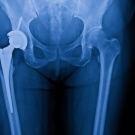

A recent study investigated whether intravenous vitamin C could reduce postoperative pain and opioid consumption in patients undergoing total hip arthroplasty.